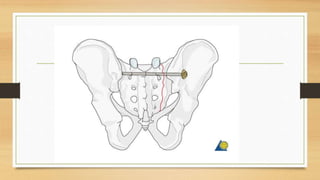

Este documento trata sobre fracturas de pelvis y acetábulo de tipos I y II. Explica la anatomía de la pelvis, incluyendo huesos, ligamentos y vasos. Describe la epidemiología, clasificación y diagnóstico de fracturas de pelvis. Detalla abordajes quirúrgicos, técnicas de osteosíntesis y fijación externa para el tratamiento de fracturas de pelvis. Finalmente, cubre posibles complicaciones.